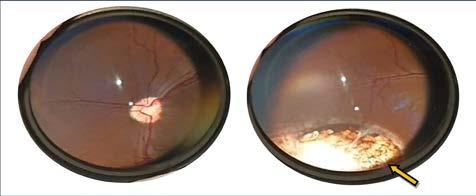

En el examen neuroftalmológico, ambos ojos se mostraron visuales con respuesta de amenaza y reflejo de deslumbramiento positivos. El reflejo pupilar directo e indirecto se observó ligeramente disminuido de manera bilateral. El test de Schirmer (Everest Tecnovet, Molins de Rei, Barcelona, España) tipo 1 mostró resultados normales de 21 mm/min en el ojo derecho y 22 mm/min en el ojo izquierdo. La presión intraocular (PIO), con tonometría de rebote (Tonovet®, Icare Finland Oy, Helsinki, Finlandia) dio resultados de 13 mmHg en el ojo derecho y 14 mmHg en el ojo izquierdo. A la exploración biomicroscópica con lámpara de hendidura (Kowa SL-17®, Kowa Company, Japón) (Fig. 1) se observó microftalmia, distiquiasis en ambos ojos, tanto en párpado superior como inferior, además de presencia de folículos en el saco conjuntival ventral. A nivel intraocular, se observó una hipoplasia de iris a las 8:00 h, y una zona compatible con membrana pupilar persistente a las 8:00 h en el ojo derecho. También pudo observarse una leve opacidad del cristalino, en cápsula/córtex anterior, a las 8:00 h. En el ojo izquierdo se observó hipoplasia de iris a las 8:00 h y a las 3:00 h. En el examen fundoscópico mediante oftalmoscopio indirecto (Heine Omega 500®, Herrsching, Alemania) y posterior dilatación con tropicamida, en ambos ojos se observó ausencia de tapetum y en el ojo derecho una zona de hipopigmentación en el epitelio pigmentario de la retina a las 6:00 h, además de una hipoplasia coroidea a las 2:00 h. En el ojo izquierdo se observó un coloboma en retina/coroides a las 2:00 h. El test de fluoresceína (Fluorescein Sodium® , Ophthalmic strips U.S.P.) dio resultados negativos bilateralmente.

CFigura 1. (A) Ojo izquierdo microftálmico con hipoplasia de iris a las 8:00 h y a las 3:00 h (véase flechas). (B) Ojo derecho microftálmico con hipoplasia de iris a las 8:00 h, y membrana pupilar persistente a las 8:00 h en el ojo derecho (véase flecha). (C) Detalle del fondo de ojo izquierdo; se observa una ausencia de tapetum y un coloboma en retina/coroides a las 2:00 h (véase flecha).

una respuesta ausente al uso de tropicamida, puso de manifiesto un patrón subalbinótico con ausencia de tapetum , además de un coloboma de coroides a las 3:00 h en el ojo derecho, y a las 9:00 h en el ojo izquierdo. También se observó un desprendimiento total de retina en el ojo izquierdo. El test de fluoresceína (Fluorescein Sodium®, Ophthalmic strips U.S.P.) dio resultados negativos en ambos ojos.

Respecto al caso 3, se observó microftalmia bilateral. Durante el examen neuroftalmológico, ambos ojos eran visuales con respuesta de amenaza y reflejo de deslumbramiento normales y reflejos pupilares no valorables debido a la presencia de corectopia bilateral. El test de Schirmer (Everest Tecnovet, Molins de Rei, Barcelona, España) tipo 1 mostró resultados normales de 18 mm/min en el ojo derecho y 25 mm/min en el ojo izquierdo. La PIO con tonometría de rebote (Tonovet®, Icare Finland Oy, Helsinki, Finlandia) dio resultados de 14 mmHg en el ojo derecho y 8 mmHg en el ojo izquierdo. A la exploración biomicroscópica (Kowa SL17®, Kowa Company, Japón) (Fig. 3) del ojo derecho se observó microftalmia, corectopia y catarata incipiente axial en córtex anterior con presencia de vacuolas

Figura 3. (A) Ojo izquierdo microftálmico con hipoplasia de iris a las 9:00 h (véase flecha azul) y un coloboma a las 9:00 h (véase flecha naranja). (B) Ojo derecho microftálmico con corectopia.

asociadas a las 8:00 h. En el ojo izquierdo se observó hipoplasia de iris a las 9:00 h y un coloboma a las 9:00 h, además de una catarata incipiente en córtex anterior a las 4:00 h. Se realizó el examen de fondo ocular mediante oftalmoscopia indirecta (Heine Omega 500®, Herrsching, Alemania), aunque el procedimiento fue dificultoso debido a la falta de respuesta pupilar tras la aplicación de tropicamida. Aun así, se observó la ausencia de tapetum y un patrón subalbinótico, además de colobomas en coroides a las 3:00 h y 9:00 h en el ojo derecho e izquierdo, respectivamente. El test de fluoresceína (Fluorescein Sodium®, Ophthalmic strips U.S.P.) dio resultados negativos en ambos ojos.

Entre otros hallazgos reportados en la literatura, se encuentran las membranas pupilares persistentes; estafilomas ecuatoriales con escleras delgadas e irregulares, donde la vascularización de la retina y coroides se encuentra muy reducida o incluso ausente; cataratas; pseudopolicoria; displasia del ángulo iridocorneal; coloboma/catarata/subluxación lenticular; hipoplasia de coroides; coloboma del nervio óptico; displasia de retina y/o desprendimiento de retina (asociado o no a hifema).6,7 Se ha descrito que la retina neurosensorial suele ser normal, pero el tapetum puede estar ausente o su espesor tener solo unas pocas células; estos cambios son bilaterales, pero no siempre simétricos.6,7 En esta serie de casos, todos presentaban microftalmia y ausencia de tapetum. Además, los casos 2 y 3 también mostraban corectopia, los casos 1 y 3 presentaban hipoplasia y coloboma de iris, así como cataratas, mientras que el caso 2 exhibía un desprendimiento unilateral completo de retina.